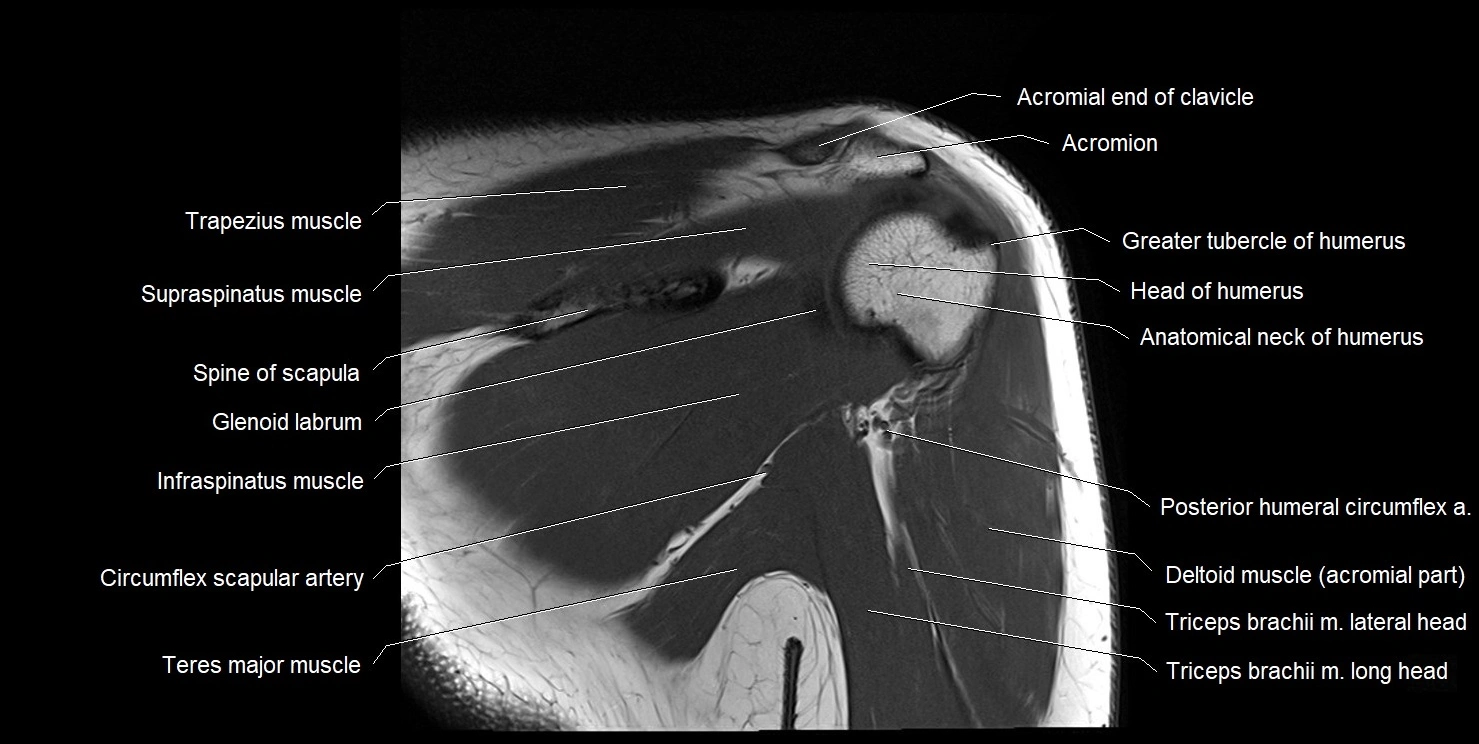

CT image

image